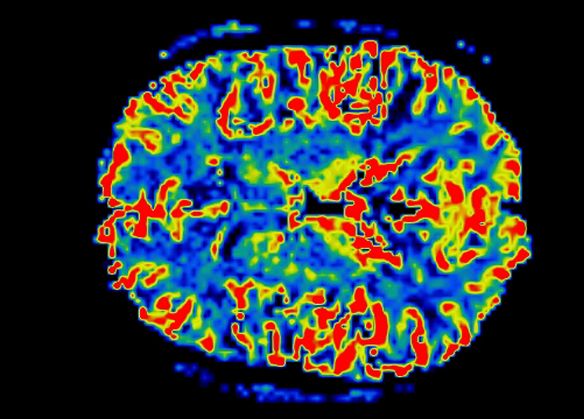

Η νόσος Πάρκινσον χαρακτηρίζεται από τη συσσώρευση της πρωτεΐνης α-συνουκλεΐνης σε σωμάτια που βρίσκονται στους νευρώνες, καθώς και από την ανεπαρκή παραγωγή και λειτουργία της ντοπαμίνης που παράγεται στους νευρώνες, όταν αυτοί σταδιακά καταστρέφονται.

Για πολλά χρόνια, οι επιστήμονες πίστευαν ότι οι νευρώνες ήταν προστατευμένοι από αυτοάνοσες επιθέσεις, ώσπου το 2014 η ερευνητική ομάδα του καθηγητή Νευροβιολογίας Ντέβιντ Σούλτσερ έδειξε ότι οι νευρώνες που παράγουν ντοπαμίνη στον εγκέφαλο (και οι οποίοι επηρεάζονται κυρίως από τη νόσο Πάρκινσον) είναι ευάλωτοι, επειδή στην επιφάνειά τους έχουν πρωτεΐνες που παραπλανούν τα Τ-κύτταρα πως πρόκειται για ξένα σώματα.

Τώρα όπως αναφέρεται στο Nature, οι ερευνητές του Ιατρικού Κέντρου του Πανεπιστημίου Κολούμπια της Νέας Υόρκης, με επικεφαλής τον δρα Σούλτσερ, διαπίστωσαν ότι τα Τ-κύτταρα του ανοσοποιητικού συστήματος μπορούν να μπερδέψουν τους κατεστραμμένους από τη νόσο Πάρκινσον νευρώνες με ξένους «επιδρομείς», με αποτέλεσμα να στρέφονται εναντίον τους.

Οι επιστήμονες ανέλυσαν δείγματα αίματος από 67 παρκινσονικούς ασθενείς και 36 συνομηλίκους υγιείς ανθρώπους και βρήκαν ότι όντως τα Τ-κύτταρα είναι δυνατό να «ξεγελασθούν» στους πρώτους και να εκλάβουν τους ντοπαμινεργικούς νευρώνες ως ξένο και δυνητικά εχθρικό σώμα, πράγμα που ενεργοποιεί το ανοσοποιητικό σύστημα.

Αυτό τους κάνει να υποθέτουν ότι η αυτοάνοση αντίδραση στην περίπτωση της νόσου Πάρκινσον εμφανίζεται, όταν οι νευρώνες του εγκεφάλου δεν είναι πια δυνατό να απομακρύνουν την αφύσικη α-συνουκλεΐνη, που αρχίζει να αυξάνεται.